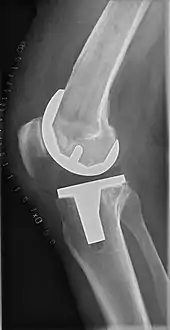

![]() |

Ángulos comúnmente medidos antes de la cirugía de reemplazo de rodilla: |

Para indicar el reemplazo de rodilla en caso de osteoartritis, su clasificación radiográfica y la gravedad de los síntomas deben ser sustanciales. Dicha radiografía debe consistir en radiografías en carga de ambas rodillas: AP, lateral y 30 grados de flexión. Es posible que las proyecciones AP y lateral no muestren un estrechamiento del espacio articular, pero la vista en flexión de 30 grados es más sensible al estrechamiento. También se utilizan proyecciones de longitud completa para ajustar la prótesis para proporcionar un ángulo neutro para la extremidad inferior distal. Dos ángulos utilizados para este propósito son:

- Ángulo cadera-rodilla-eje (CRE),[8] un ángulo formado entre una línea que pasa por el eje longitudinal de la diáfisis femoral y su eje mecánico, que es una línea desde el centro de la cabeza femoral hasta la muesca intercondilar de la diáfisis femoral. fémur.[10]

- Ángulo cadera-rodilla-tobillo (CRT),[9] que es un ángulo entre el eje mecánico femoral y el centro de la articulación del tobillo.[10] Normalmente se encuentra entre 1.0° y 1.5° de varo en adultos.[11]